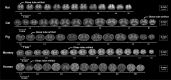

The overall goal of this work was to create a high-resolution MRI atlas of the lumbosacral enlargement of the spinal cord of the rat (Sprague-Dawley), cat, domestic pig, rhesus monkey, and human. These species were chosen because they are commonly used in basic and translational research in spinal cord injuries and diseases. Six spinal cord specimens from each of the studied species (total of 30 specimens) were fixed, extracted, and imaged. Sizes of the spinal cord segments, cross-sectional dimensions, and locations of the spinal cord gray and white matter were quantified and compared across species. The lumbar enlargement spans spinal cord levels L3-S1 in rats, L4-S1 in cats, L3-S1 in pigs, L2/L3-L7/S1 in monkeys, and T12/L1-S1/S2 in humans. The enlargements in pigs and humans are largest and most similar in size (length and cross-sectional area); followed by monkeys and cats; and followed by rats. The obtained atlas establishes a neuroanatomical reference for the intact lumbosacral spinal cord in these species. It can also be used to guide the planning of surgical procedures of the spinal cord and technology design and development of spinal cord neuroprostheses, as well as precise delivery of cells/drugs into target regions within the spinal cord parenchyma.